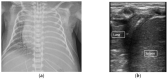

A neonatal point-of-care ultrasound has multiple applications, but its use has been limited in neonatal intensive care units in the Unites States. An increasing body of evidence suggests that lung ultrasound performed by the neonatologist, at the bedside, is reliable and accurate in differentiating neonatal respiratory conditions, predicting morbidity, and guiding invasive interventions. Recent research has shown that a lung ultrasound can assist the clinician in accurately identifying and managing conditions such as respiratory distress syndrome, transient tachypnea of the newborn, and bronchopulmonary dysplasia. In this review, we discuss basic lung ultrasound terminology, evidence for applications of neonatal lung ultrasound, and its use as a diagnostic and predictive tool for common neonatal respiratory pathologies.